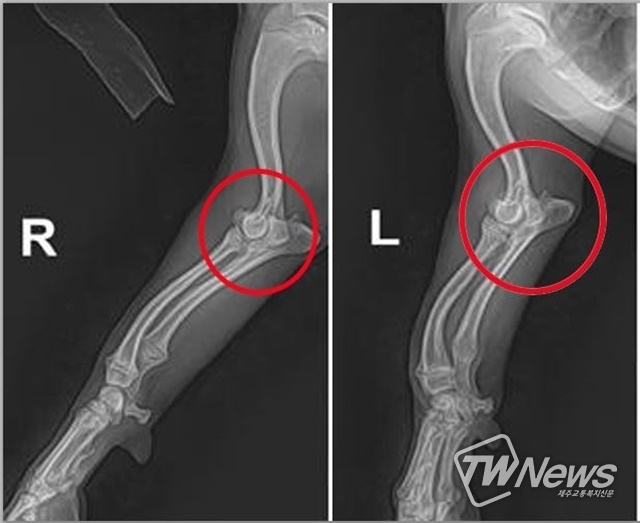

실제로, X-ray를 통해,척골 성장판 조기폐쇄증에 걸린 동물들을 살펴보면, 팔꿈치 관절 이탈구 소견이 있거나 ulna (척골) 성장판 조기 폐쇄를 확인할 수 있다. 앞다리 뼈에서 척골과 radius (요골)의 균형이 맞춰지지 않는 것을 확인할 수 있다.